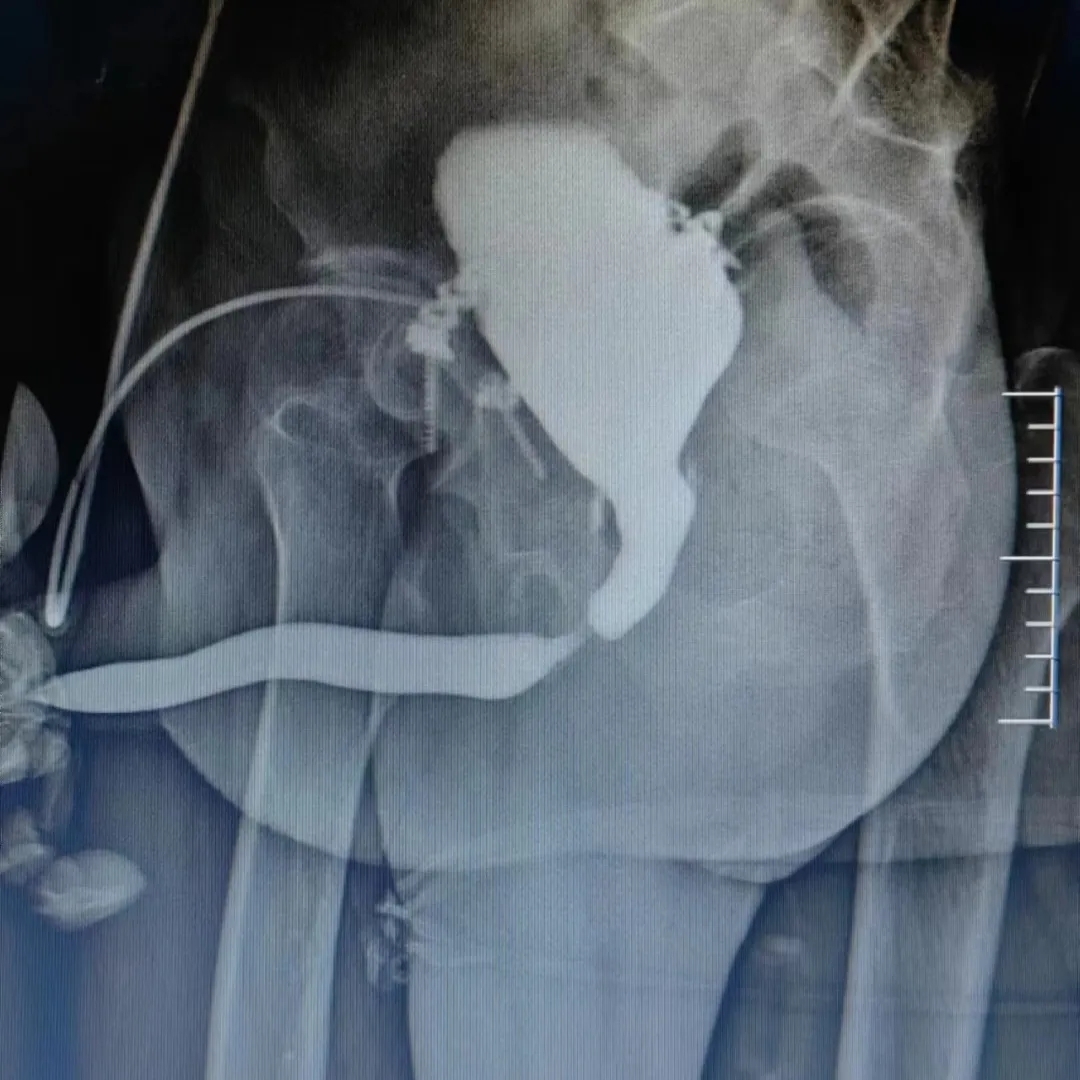

“尿道狹窄”多指由外傷、感染及醫(yī)原性損傷導(dǎo)致患者不能自行排尿的病癥,嚴(yán)重者需要終生攜帶尿袋,給患者帶來(lái)巨大痛苦。黑龍江省第二醫(yī)院泌尿外科胡忠良主任于2013年率先在省內(nèi)開(kāi)展了“尿道重建技術(shù)”,采用“舌粘膜、口腔粘膜尿道成型”、“帶蒂皮瓣尿道重建”及“經(jīng)會(huì)陰尿道端端吻合”等術(shù)式,來(lái)治療尿道狹窄和閉鎖,取得了良好效果。現(xiàn)已完成手術(shù)500余例,治愈率達(dá)85%以上。王先生就是慕名前來(lái)的患者之一。他曾經(jīng)歷過(guò)嚴(yán)重的車(chē)禍,造成了骨盆骨折、尿道斷裂。長(zhǎng)時(shí)間無(wú)法自行排尿讓王先生痛苦不堪,在外院進(jìn)行了膀胱造瘺術(shù)治療后,每月仍需更換造瘺管,生活質(zhì)量嚴(yán)重下降。在經(jīng)過(guò)一番咨詢(xún)后來(lái)到黑龍江省第二醫(yī)院。經(jīng)過(guò)檢查,王先生確診為“膜部尿道閉鎖(長(zhǎng)度1cm)”。胡忠良主任在進(jìn)行了充分的術(shù)前準(zhǔn)備后,為王先生進(jìn)行了尿道重建手術(shù),術(shù)后患者排尿非常順暢,完全恢復(fù)到了受傷前的狀態(tài),造影顯示尿道連續(xù)性完好,幾乎無(wú)手術(shù)痕跡。如今,隨著技術(shù)水平逐漸提高,省二院泌尿外科追求的不再僅僅是能夠使患者維持排尿,而是手術(shù)的精準(zhǔn)性、形態(tài)學(xué)上的“無(wú)痕”化,功能的保護(hù)和康復(fù),使患者恢復(fù)最佳狀態(tài),最大程度上提高生活質(zhì)量。